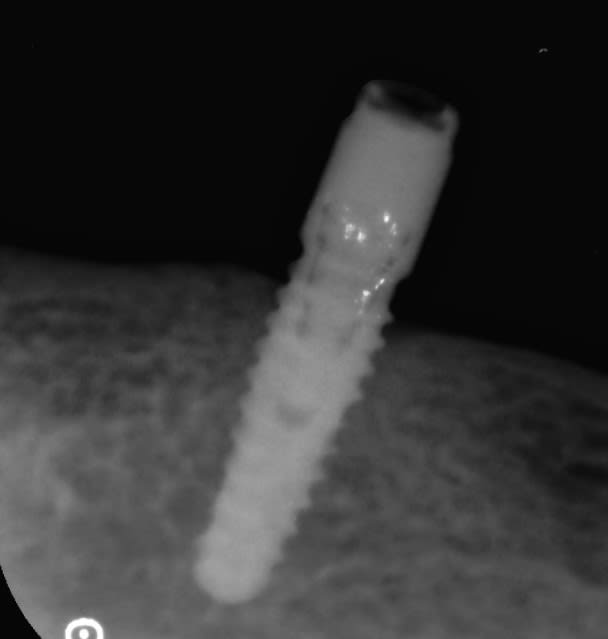

Reconnaissance implants pour changement des locators usés suite à 27 années de bons service

je suis à la recherche de la référence de la connectique implantaire pour pouvoir changer les locators usés sur ces implants.

22b9dhm6upuzajxdjyprvucw1l02 - Eugenol

B4oull3wo3s1m6mywyrulgdd143p - Eugenol

Photo pluton1b h9n4ea - Eugenol

t'as rien de plus net?

malheureusement non, ce n'est pas top comme radio.